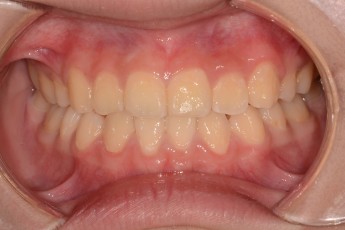

Before & After

Before

After